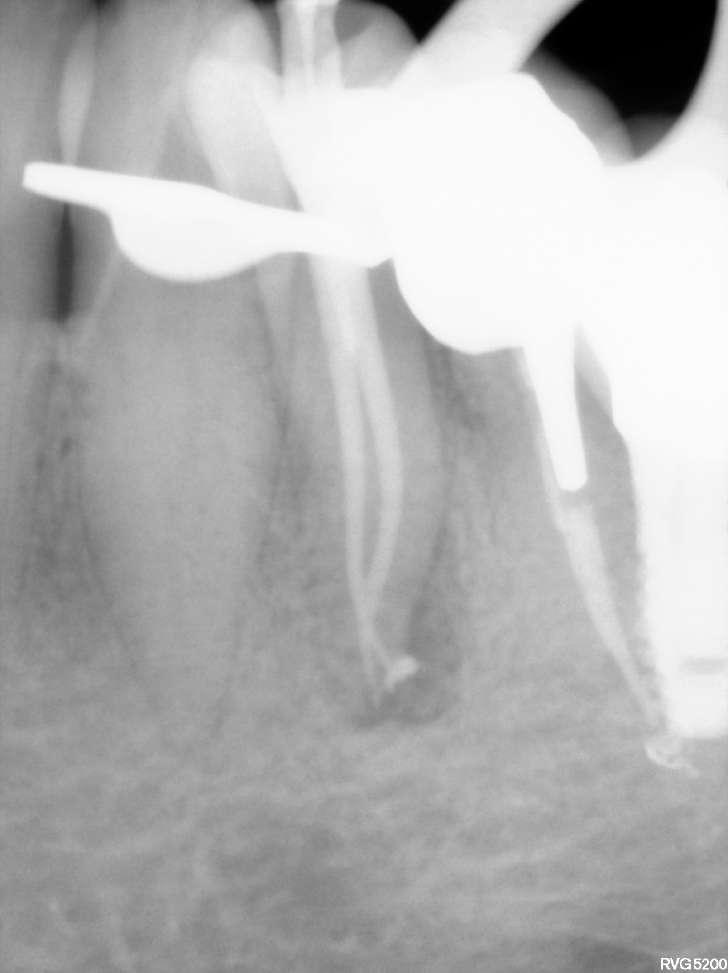

Divergierende Kanäle (zwei Kanäle, die zusammen beginnen und sich dann im mittleren / apikalen Teil der Wurzel trennen) stellen ein klinisches Problem in der Endodontie dar, insbesondere bei der Verwendung traditioneller NiTiInstrumente. Aufgrund des superelastischen Verhaltens der Legierung können die Instrumente dem gleichen Kanal folgen (und zwar dem, der gerader ist) aber es ist schwieriger, den zweiten zu finden, insbesondere dann, wenn man den Eingang unmöglich wegen seiner Tiefe in der Wurzel sehen kann.

Der vorliegende Fall zeigt den klinischen Vorteil der Verwendung einer Einzelfeil-Reziprokationstechnik mit einer wärmebehandelten vorgebogenen martensitischen Feile (Edge One Fire) bei der Behandlung divergierender Kanäle auf.

Untere Prämolaren können manchmal zwei oder drei Kanäle aufweisen. Eine solche ungewöhnliche Anatomie ist oft mit engen, stark gekrümmten, konfluenten oder divergierenden Kanälen verbunden. Der letzte Fall ist sehr komplex und erfordert in der Regel den Einsatz von Instrumenten, welche in zwei verschiedenen Kanälen ( daher flexibel und präbendal ) mit unterschiedlichen Winkelstellungen ausgerichtet werden können. Ein angemessener Gleitpfad hilft auch bei der NiTi-Formung, er löst aber nicht immer das Problem. Daher wurde im vorliegenden Fall die primäre EinzelfeileReziproziertechnik EOF verwendet. Die Instrumente wurden in ihrem apikalen Teil vorgeformt, in die beiden verschiedenen Kanäle eingeführt und dann aktiviert. Die Wahl der Instrumente war effektiv, weil die mechanischen Eigenschaften des EOF-Primärs (flexibel und vorgebogen) es ermöglichen, präzise und einfach in jeden Kanal eingeführt zu werden und diese dann zu behandeln. Die Verwendung einer einzigen Feiltechnik ermöglichte es, sich der Herausforderung eines divergierenden Kanals nur einmal zu stellen, was Zeit spart und die Komplexität reduziert. Die Verwendung traditioneller Instrumente kann in vielen Fällen helfen, den Weg mit kleineren und flexibleren Instrumenten zu finden, aber nicht mit größeren. Durch die Verwendung von nur einer Feile erwies sich das gesamte Verfahren als einfacher und schneller, sodass beide Kanäle korrekt geformt, gereinigt und abgedichtet werden konnten.

Eine Single-File-Reziprozierungstechnik mit einer wärmebehandelten vorgebogenen martensitischen Feile (Edge One Fire) erwies sich als ausgezeichnete, einfache und schnelle Option für die Instrumentierung von divergierenden Kanälen.

Komplexe Kanalanatomien erfordern den rationalen Einsatz von NITIInstrumenten, indem die beste Option für den Fall in Bezug auf Effizienz, Sicherheit und Einfachheit ausgewählt wird. Die mechanischen Eigenschaften von EOF ermöglichen es, divergierende Kanäle mit großer Wirksamkeit zu behandeln, wobei iatrogene Fehler oder Komplikationen vermieden werden können.